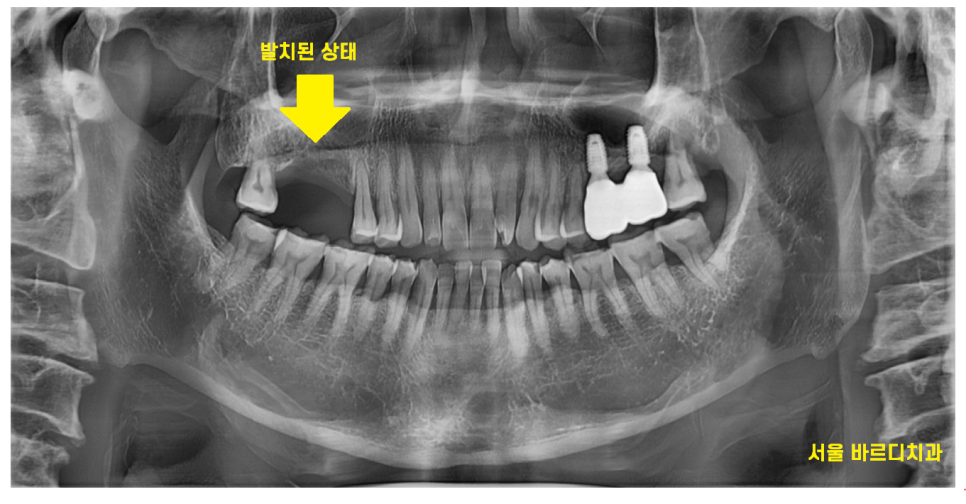

오른쪽 위에 부분은 발치 된지 오래된 상태

문제가 있어보이는 치아 2개

너무 아파서 발치를 원하셨습니다.

전남 완도 치과에서도

뽑아야한다 했는데

약을 먹고 버티고 계셨다 하셨습니다.

뿌리쪽 충치라 예후도 안좋고

염증으로 인하여 치아가 흔들려서

발치를 해야한다 환자분을 설득 드렸죠..